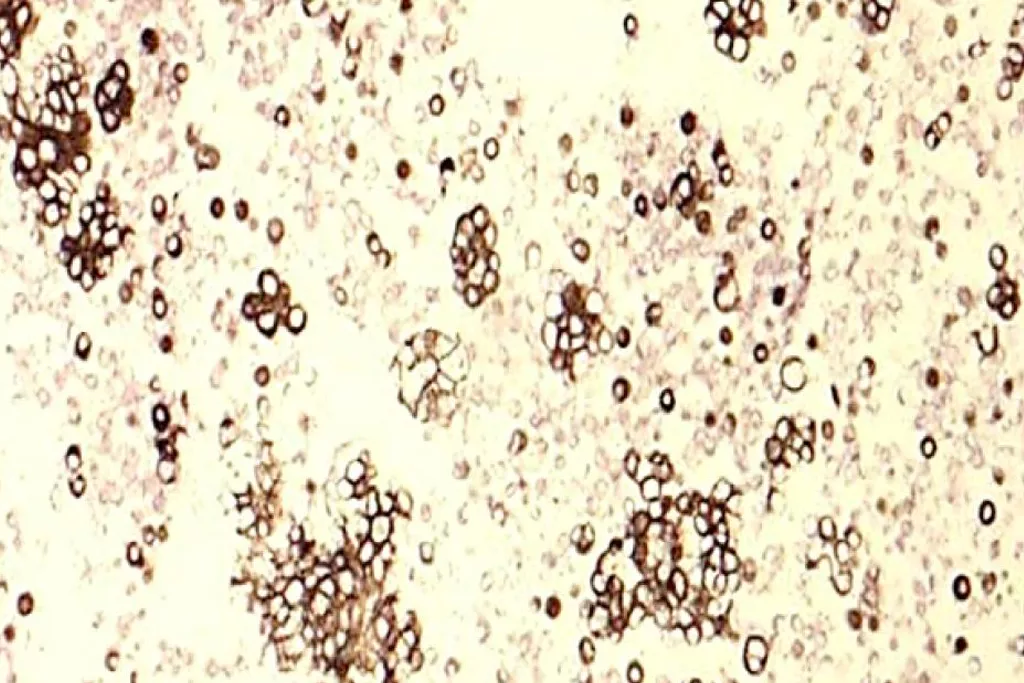

Image Gallery2

2. Image Courtesy of Cytology Dept. Groningen University Hospital, Netherlands